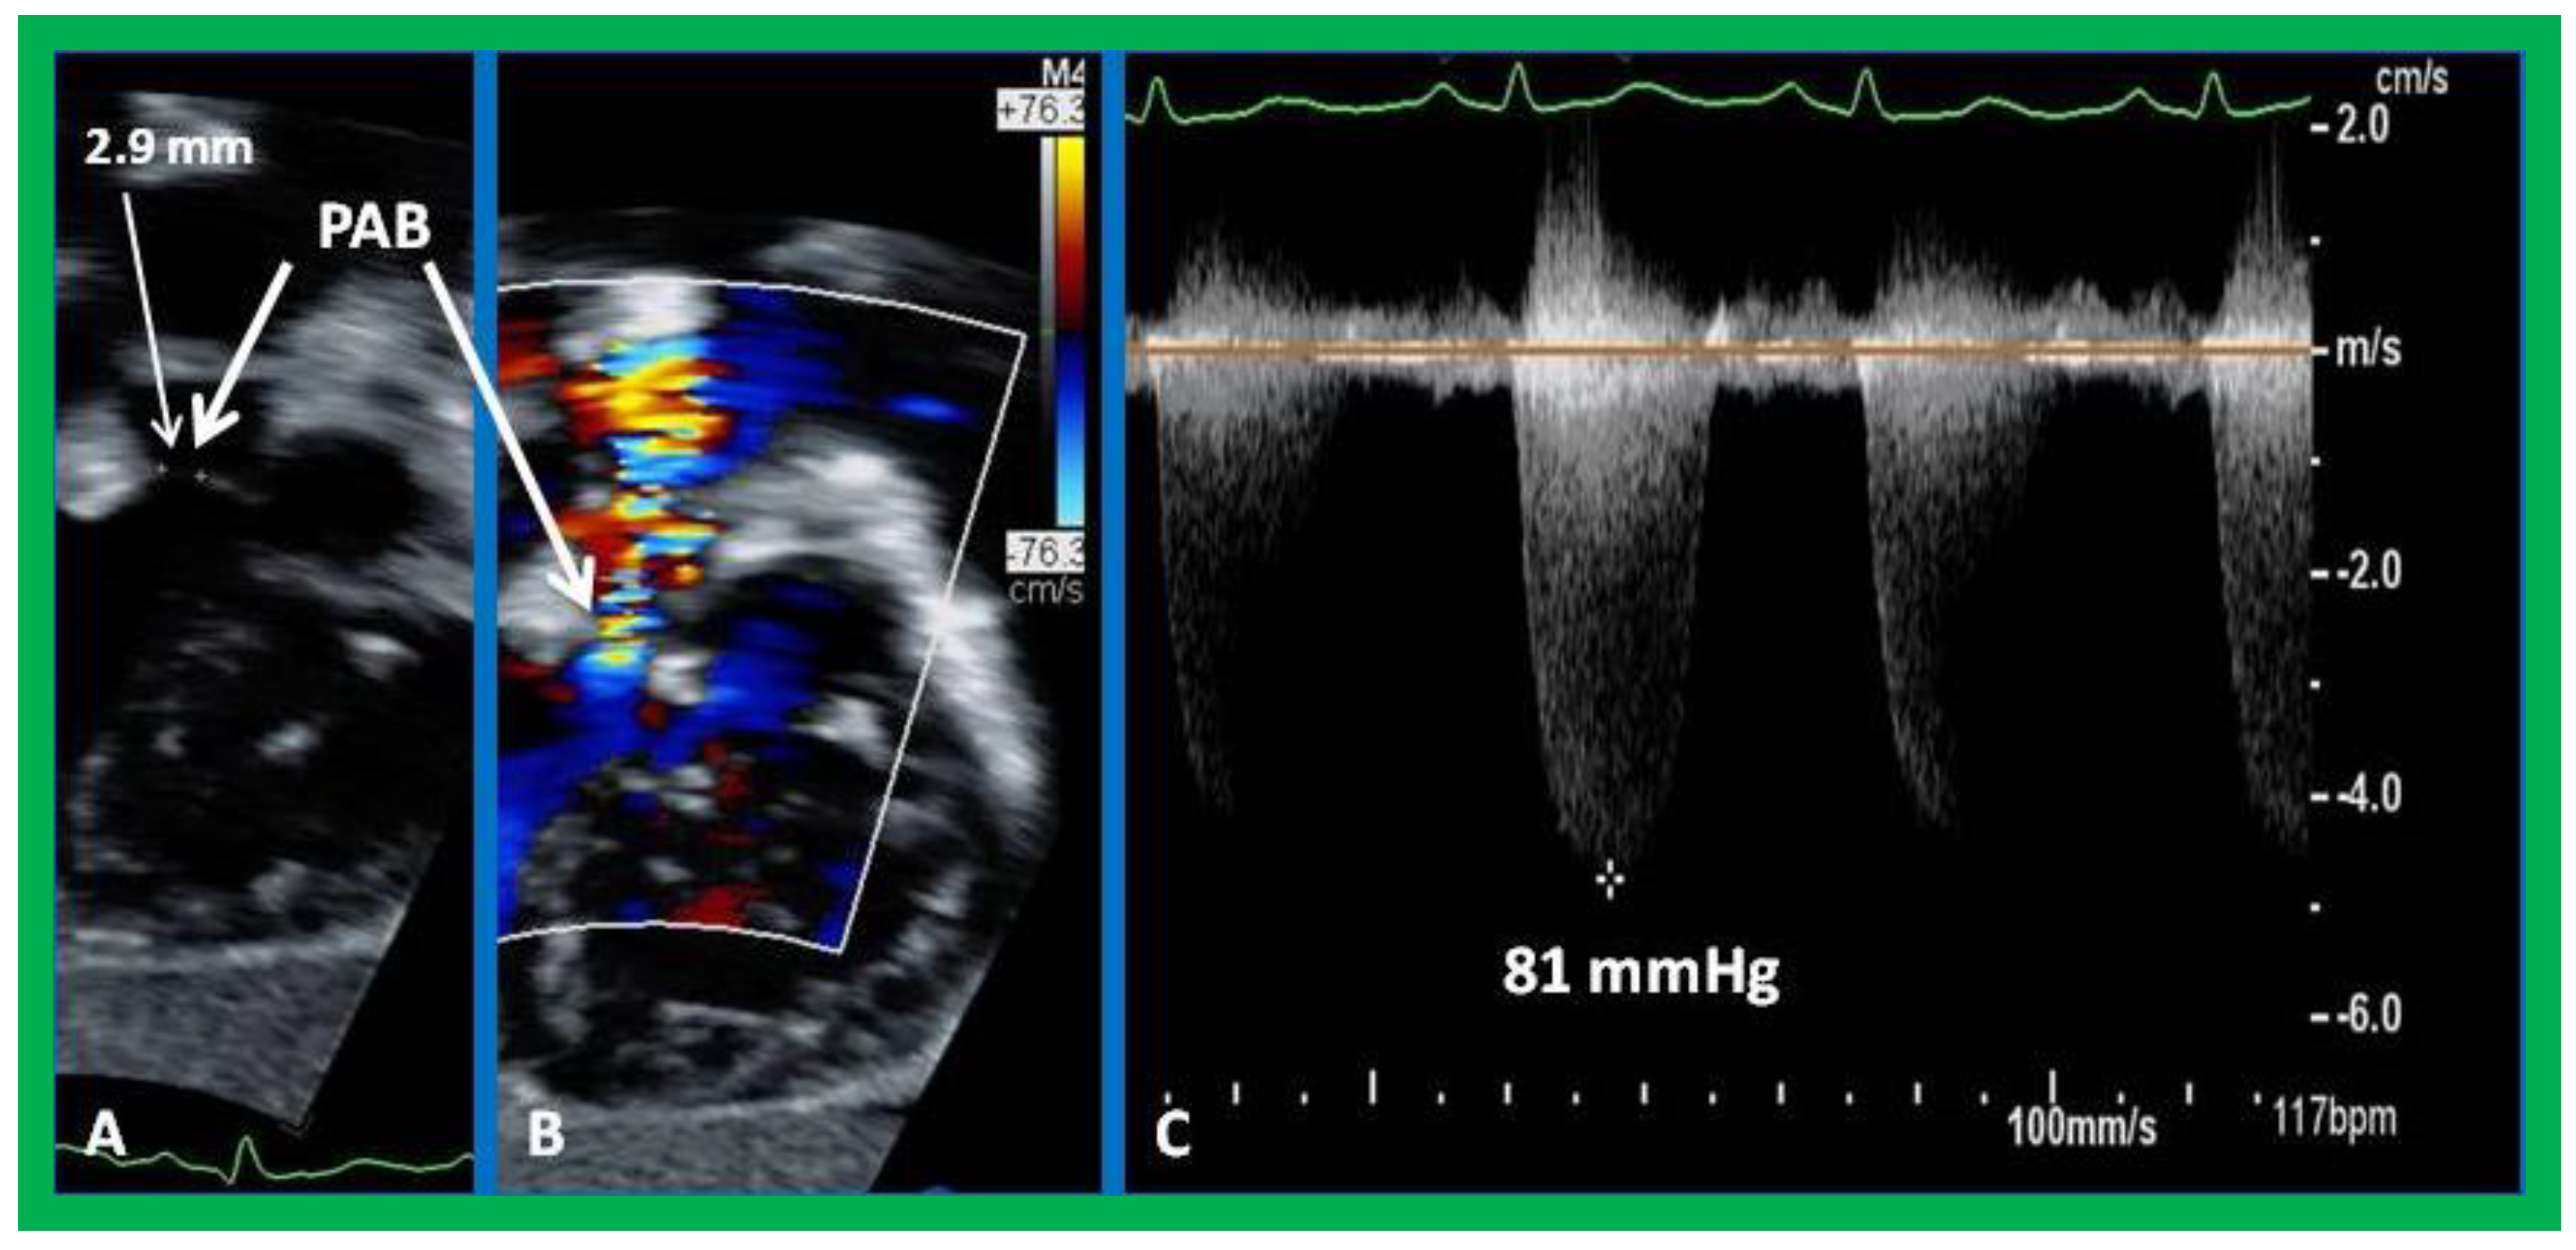

8. Echocardiogram

9. Cardiac Catheterization with Angiography, Magnetic Resonance Imaging (MRI) and Computed Tomography (CT)